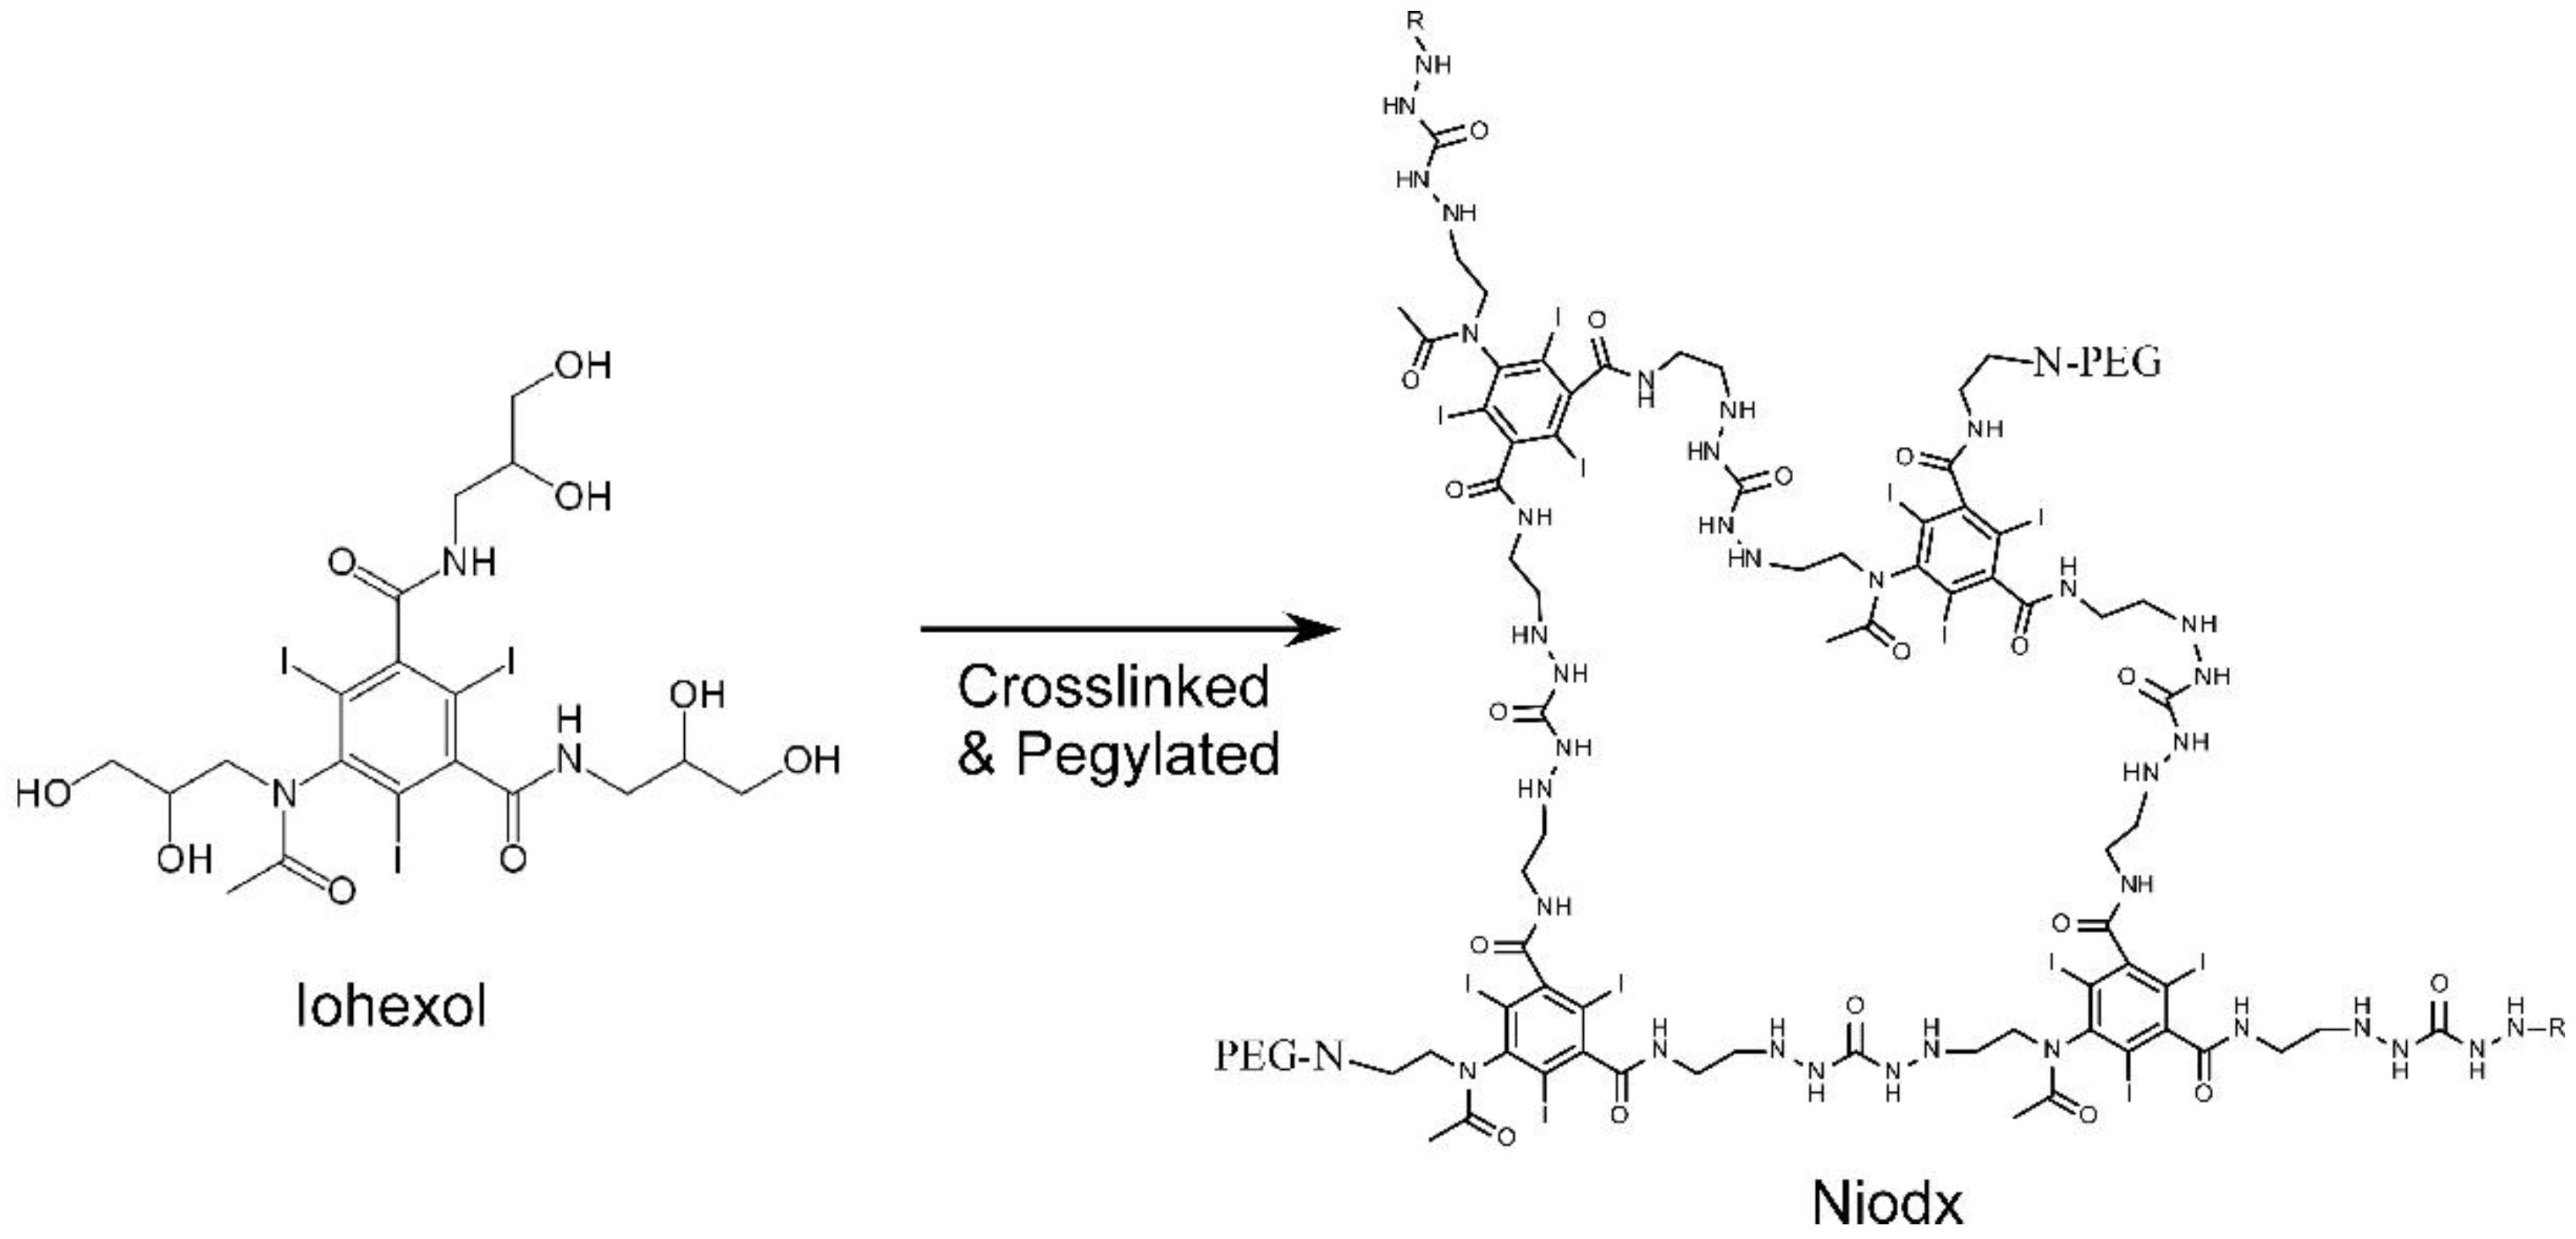

1.3. Iodine Nanoparticles

1.4. Iodine Nanoparticle Imaging